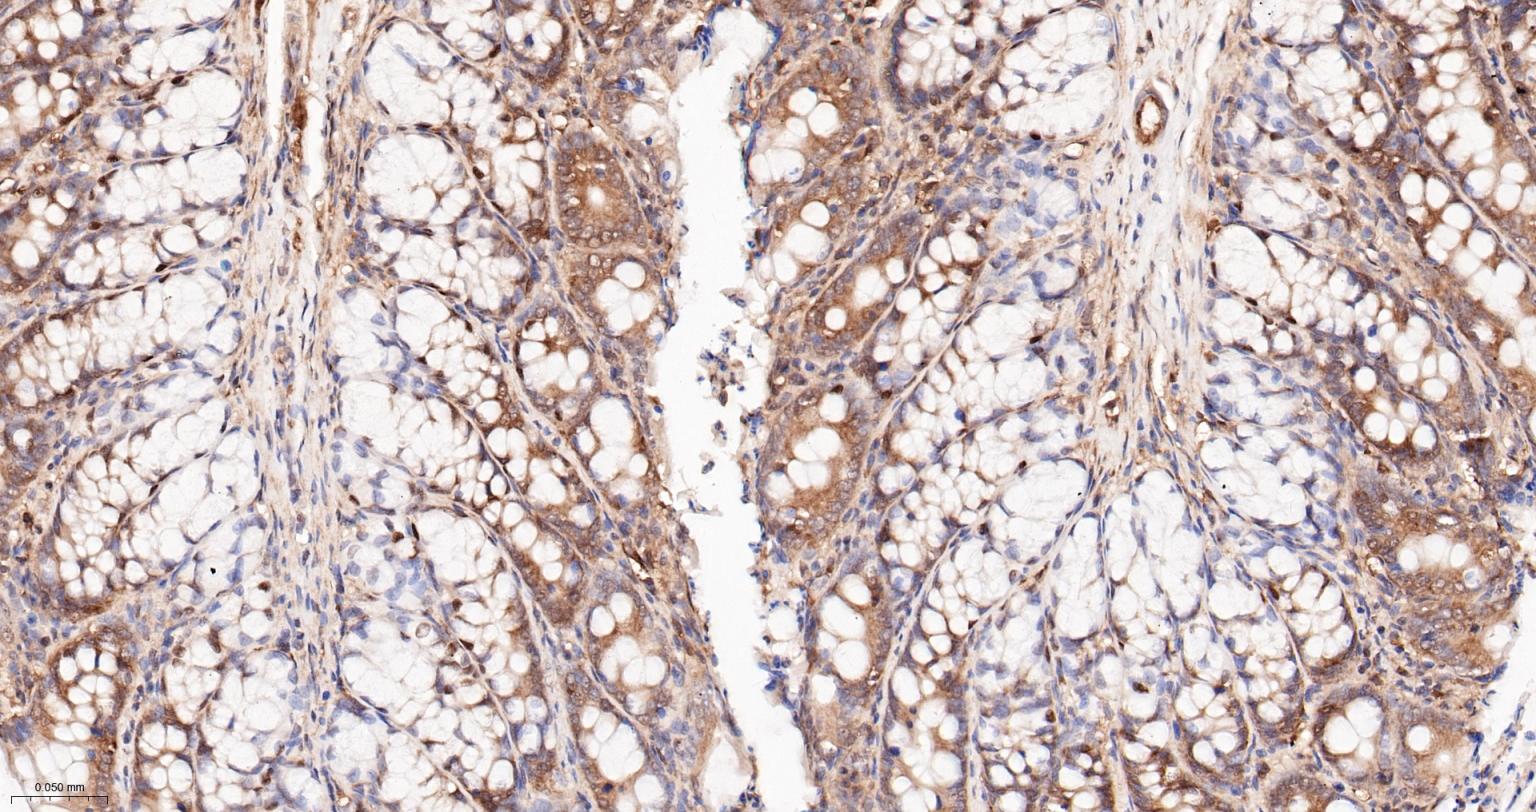

Paraformaldehyde-fixed, paraffin embedded Human Colon Cancer; Antigen retrieval by boiling in sodium citrate buffer (pH6.0) for 15 min; Antibody incubation with Hsp90 alpha Monoclonal Antibody, Unconjugated(bsm-52353R) at 1:200 overnight at 4°C, followed by conjugation to the SP Kit (Rabbit, SP-0023) and DAB (C-0010) staining.

Paraformaldehyde-fixed, paraffin embedded Human Colon; Antigen retrieval by boiling in sodium citrate buffer (pH6.0) for 15 min; Antibody incubation with Hsp90 alpha Monoclonal Antibody, Unconjugated(bsm-52353R) at 1:200 overnight at 4°C, followed by conjugation to the SP Kit (Rabbit, SP-0023) and DAB (C-0010) staining.